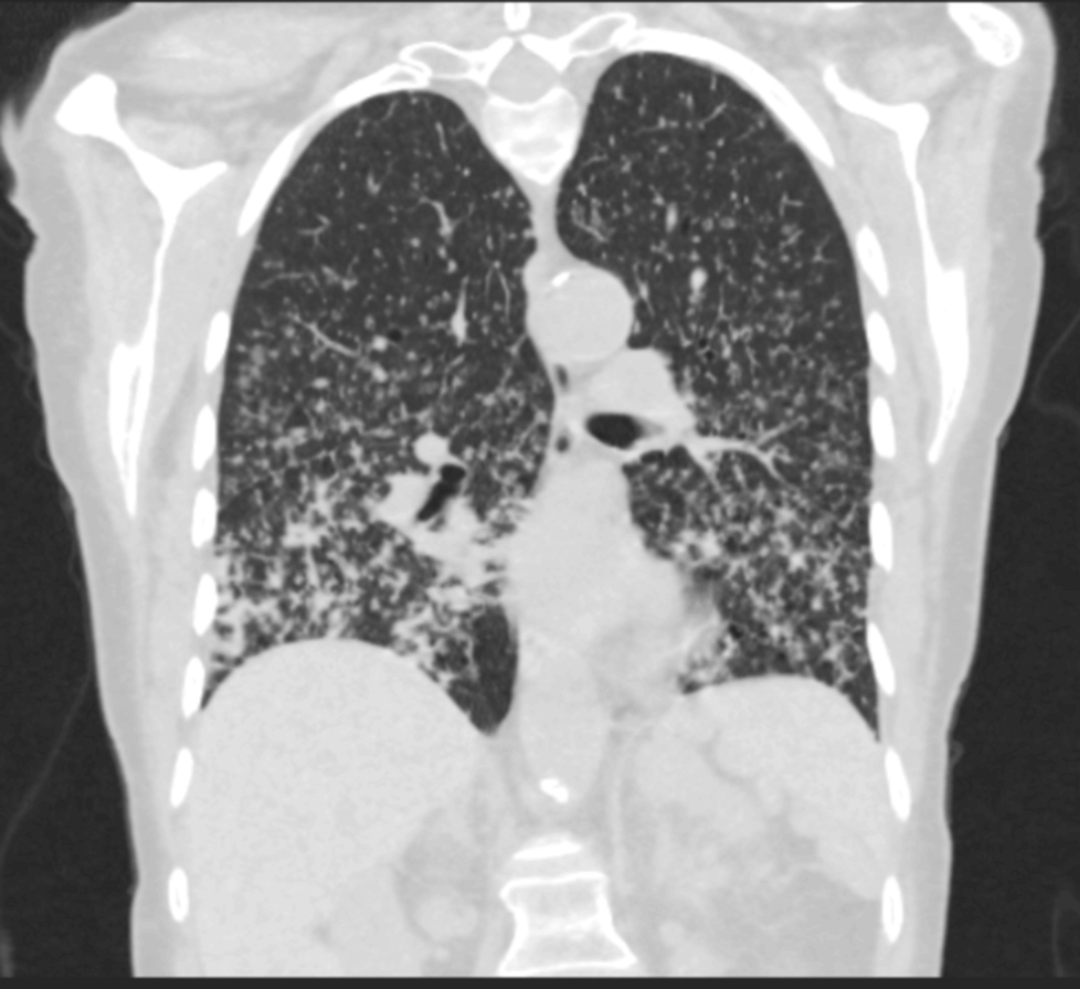

影像学检查:胸部X线提示双肺纤维化改变(图1);胸部CT显示双肺多发小叶中心性结节,以支气管血管周围、裂周和胸膜下区域为主,下叶为著(图2)。

图2 胸部CT